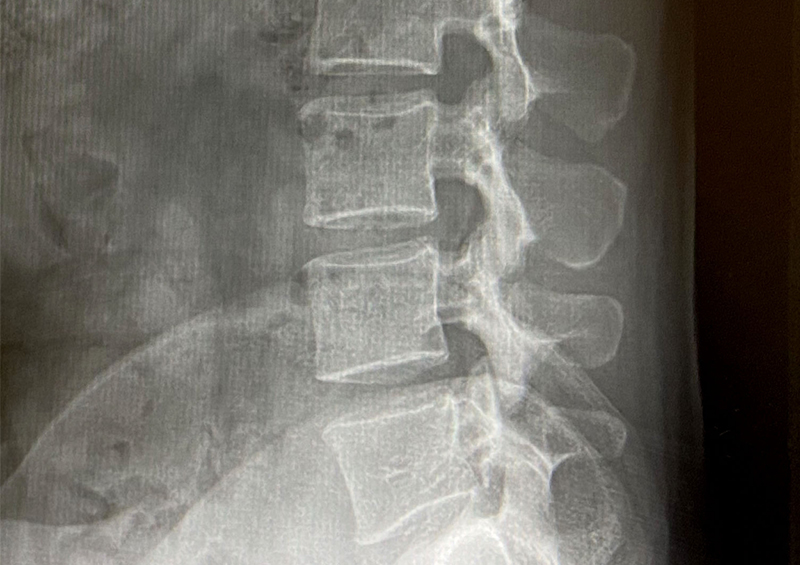

2,レントゲン検査

当院では、まずレントゲン検査をします。この検査では腰椎の骨の状態がよくわかります。

たとえば、腰椎辷り症という病気で腰椎がずれているとか骨折や、骨腫瘍など異常陰影などや骨粗鬆症があるとかがよくわかります。しかしあくまで骨の状態が主目的で、神経、筋肉とかは映し出されません。